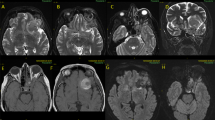

This case report illustrates a patient with a unilateral localized epidural schwannoma at C1 – 2 level, showing contralateral spinal cord symptoms and signs. The clinical presentation was compared with the neuroradiological examinations showing an epidural cord tumor at the right C1 – C2 level. However, the neurological examination revealed contralateral hemiparesis and ipsilateral hemihypoalgesia, indicating a contralateral Brown – Sequard syndrome. We presumed with this slow growing tumor, contralateral cord involvement may result from counter pressure on the spinal cord, which may be generated by cord deviation and by frequent neck rotation.